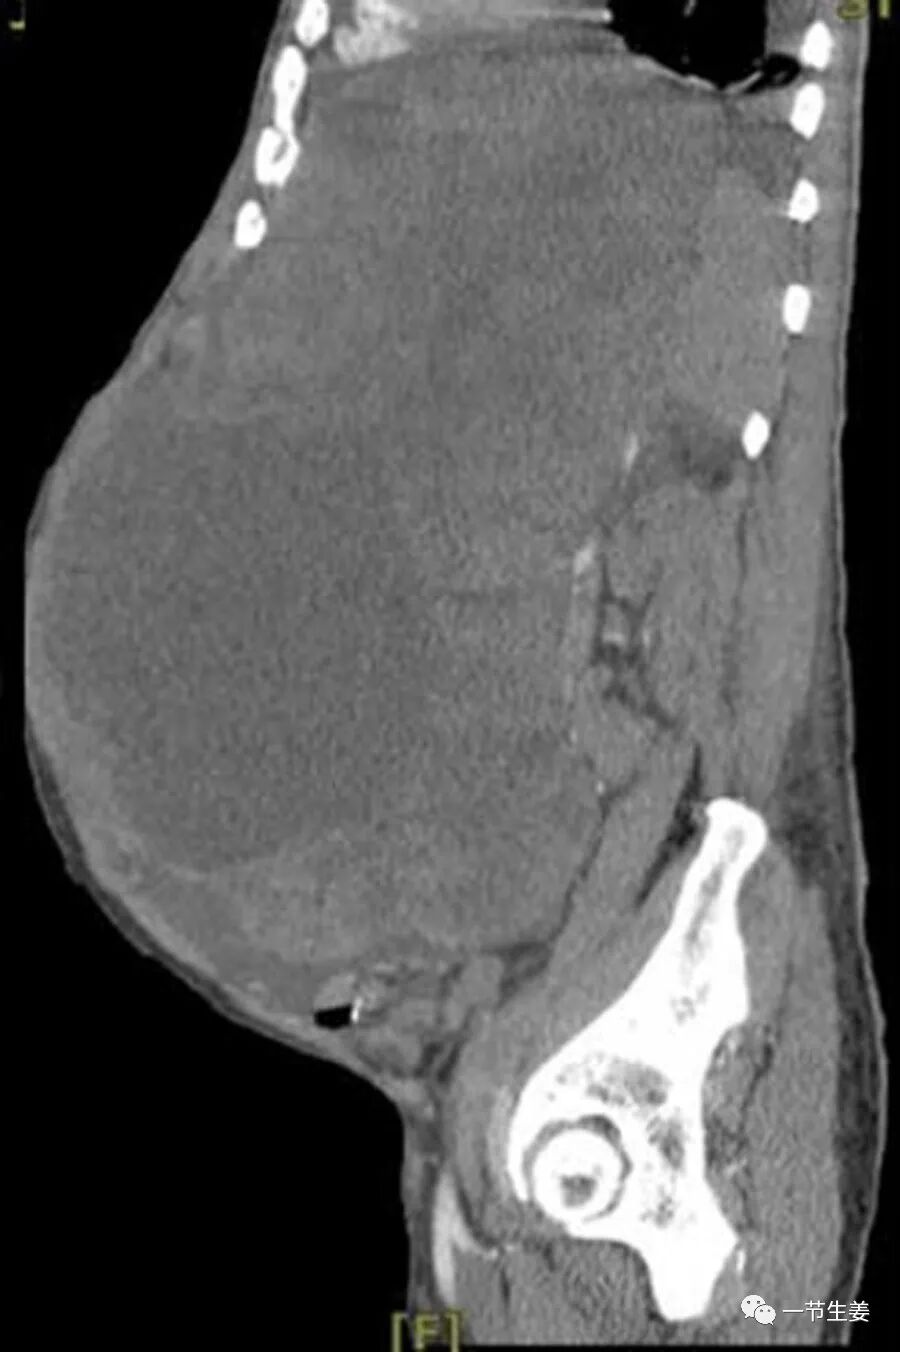

切除这个肿瘤,医生花了7个小时的时间,患者也失去了3升血,切下的肿瘤形状不规则,重量是18.5公斤。女性怀孕的孕期也是9个月,但是婴儿出生时体重一般就是3~4公斤。患者的这个肿瘤,不是胖若两人,而是重如4~5个刚出生的婴儿。